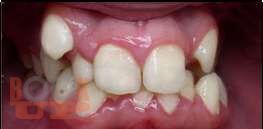

В пособии представлены вопросы этиологии, клиники, диагностики, лечения зубочелюстных аномалий и методы их комплексной профилактики.

Включает в себя тему изменений в околозубных тканях в процессе ортодонтического лечения, описаны ортодонтичекие силы, различные теории перестройки костной ткани, изменения в ВНЧС при перемещениях нижней челюсти. Описаны причины рецидивов как таковых, так и отдельных нозологических форм зубочелюстных аномалий, а так же рекомендации для надежного ретенционного периода и уменьшению рисков возникновения рецидива. Учебное пособие предназначено для студентов, обучающихся по специальности 31.05.03 «Стоматология».